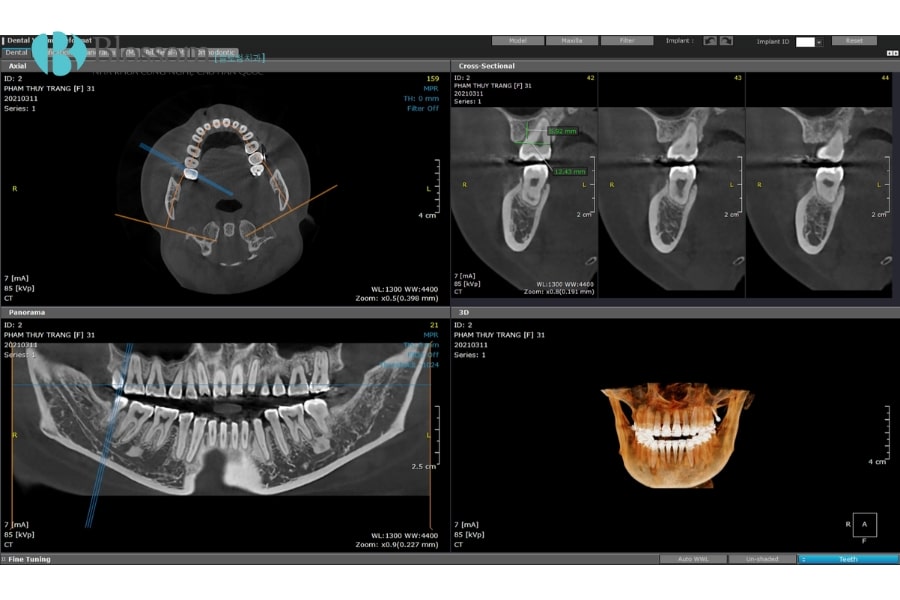

CT Cone Beam giúp đánh giá chính xác chất lượng và khối lượng xương hàm, vị trí dây thần kinh và mạch máu, từ đó lập kế hoạch cấy ghép Implant an toàn. Hình ảnh 3D cho phép chọn đường kính Implant phù hợp, dự đoán có cần ghép xương và tránh chèn ép các cấu trúc quan trọng như xoang hàm trên hay dây thần kinh hàm dưới, đảm bảo tuổi thọ lâu dài của trụ Implant.

- Lập kế hoạch điều trị chính xác: Hình ảnh 3D toàn diện giúp bác sĩ đánh giá mật độ xương, vị trí răng, đường đi dây thần kinh, từ đó lên kế hoạch cấy ghép Implant, chỉnh nha hoặc nhổ răng khôn an toàn.

- Giảm thiểu rủi ro phẫu thuật: Cho phép xác định chính xác các cấu trúc giải phẫu quan trọng, hạn chế tối đa biến chứng trong các ca tiểu phẫu và phẫu thuật nha khoa.